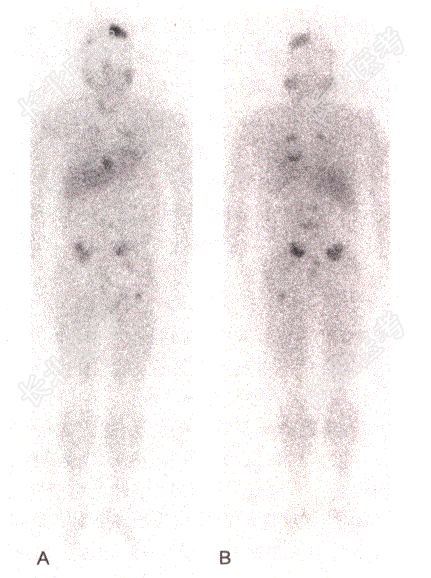

- [材料题] 患者,男,62岁,发作性头痛、心悸、手抖、大汗、呕吐2年余;24h尿儿茶酚胺明显升高。CT示多发骨转移。14年前于外院行左侧肾上腺嗜铬细胞瘤切除术;术后仍有高血压。 肾上腺髓质显像:全身显像示头部、胸部、腹部可见多个大小不等、形状不一的异常放射性浓聚区。